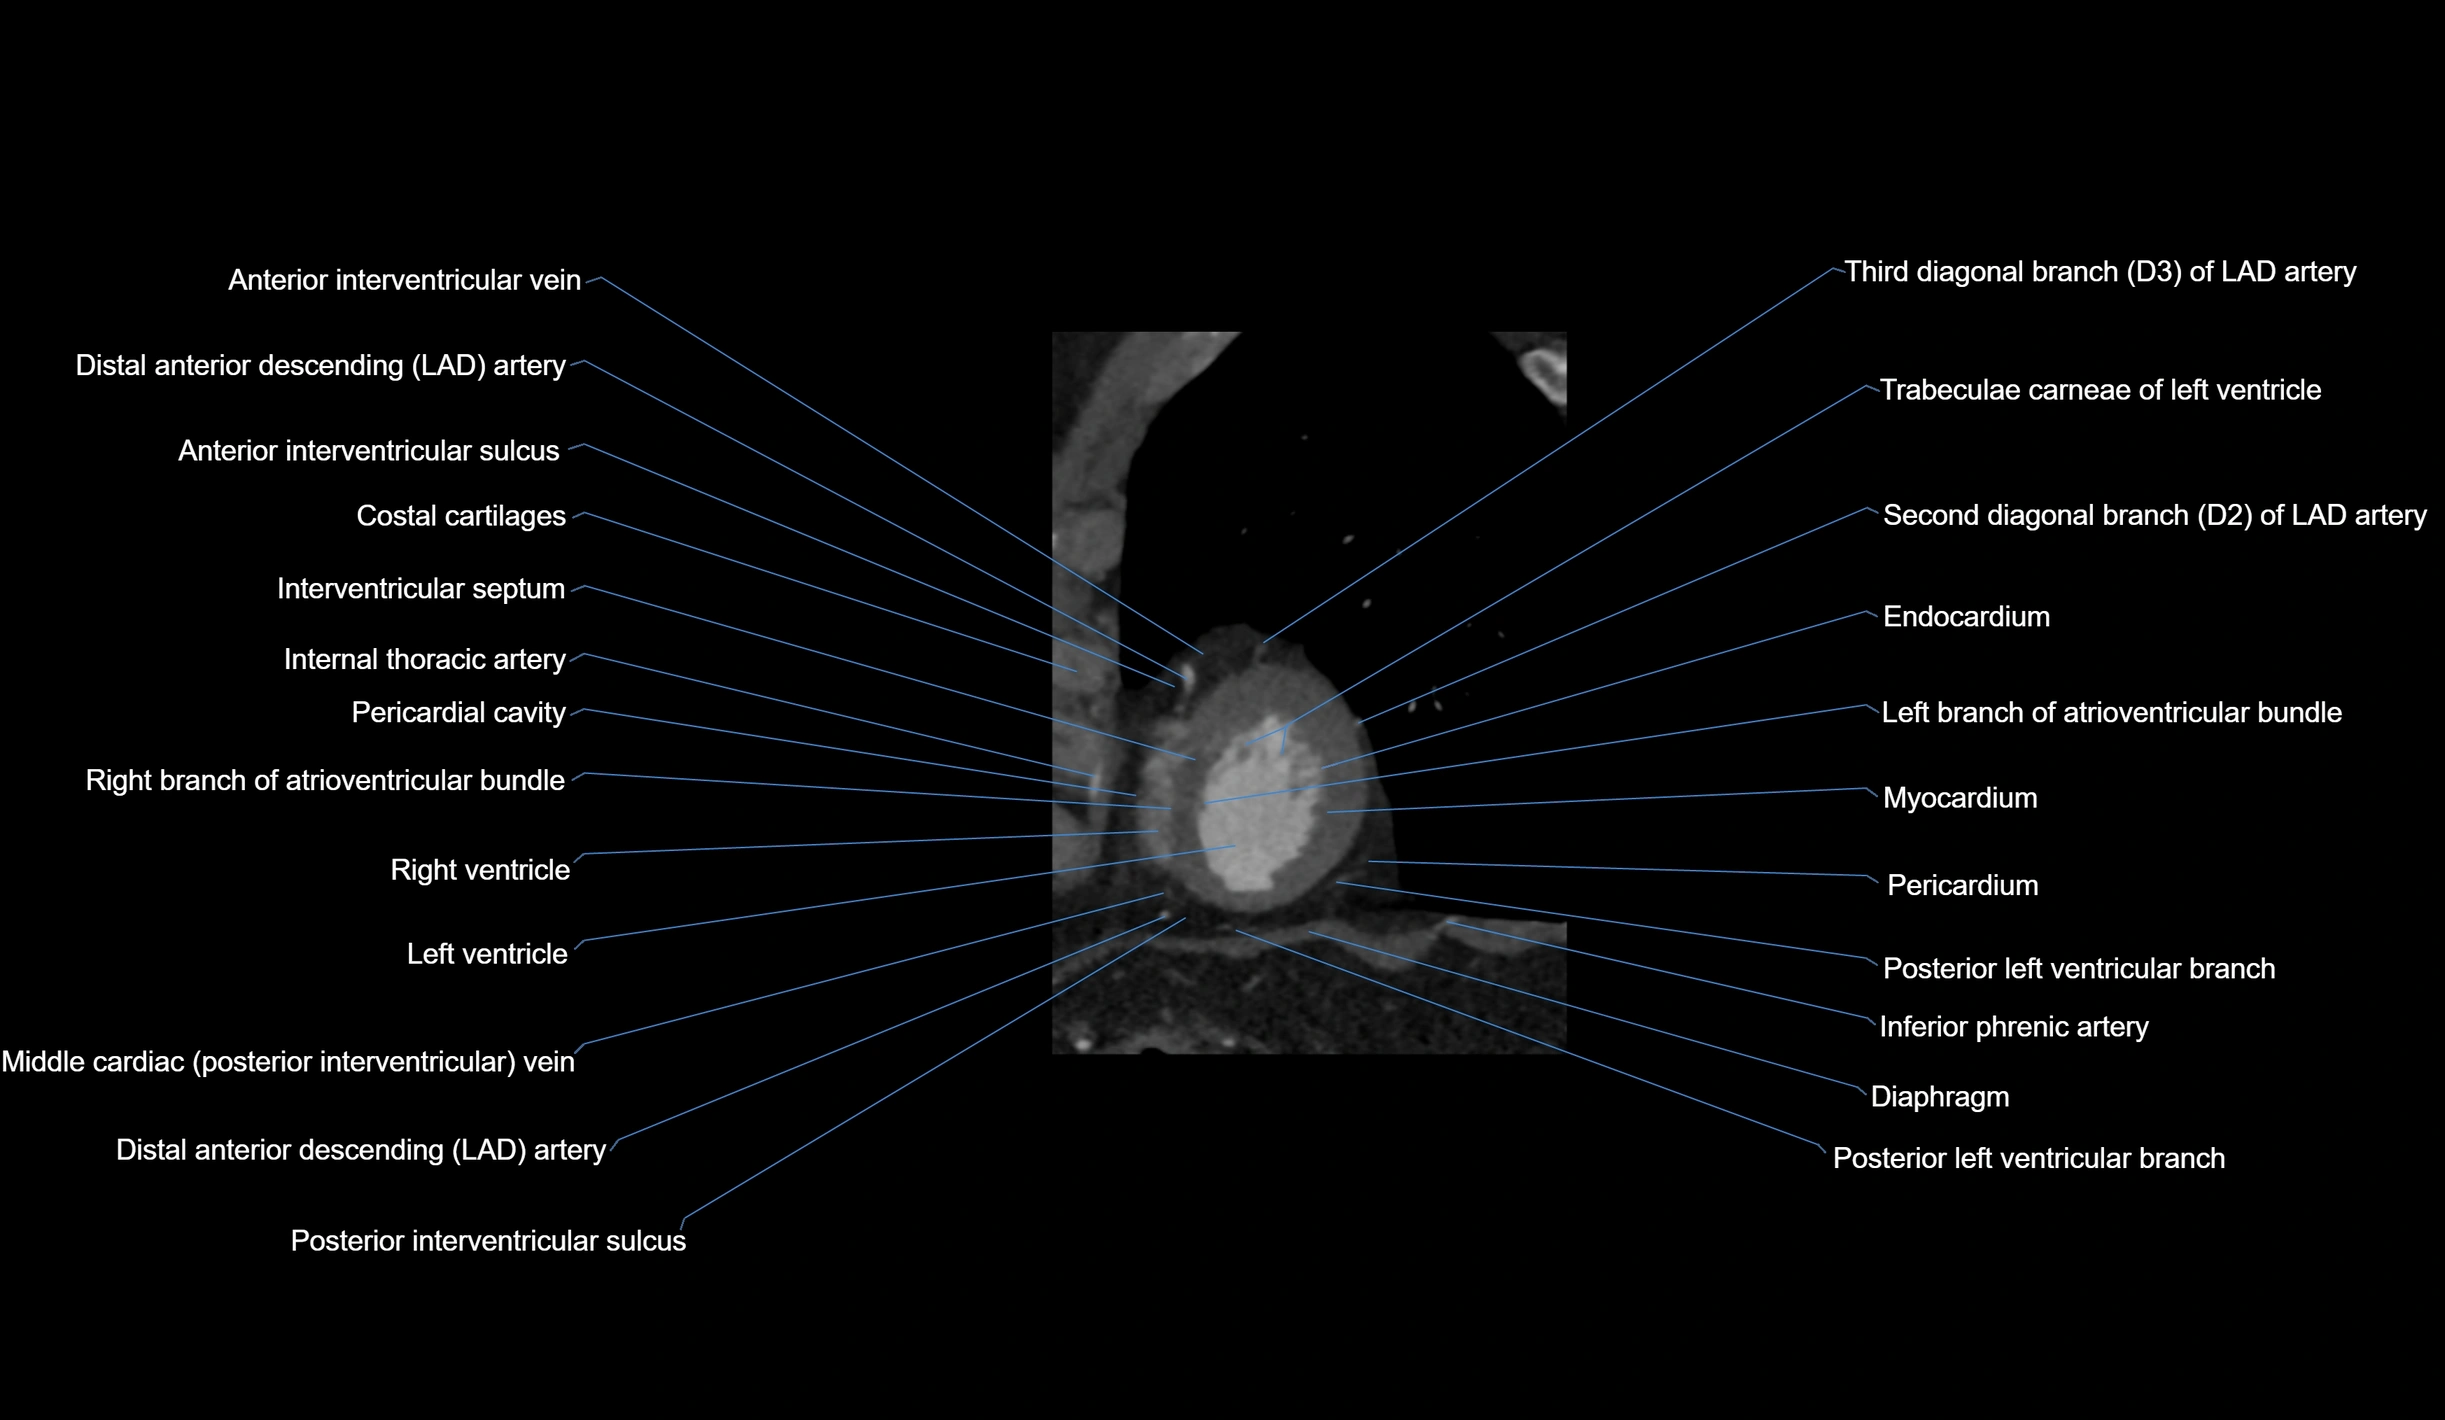

- Costal cartilages

- Diaphragm

- Distal left anterior descending artery (dLAD)

- Endocardium

- Inferior phrenic artery

- Interventricular Septum

- Left branch of atrioventricular bundle

- Left ventricle

- Middle cardiac vein

- Myocardium

- Pericardium

- Posterior interventricular sulcus

- Right branch of atrioventricular bundle

- Right ventricle

- Second diagonal branch (D2) of LAD

- Third diagonal branch (D3) of LAD

- Trabeculae carneae